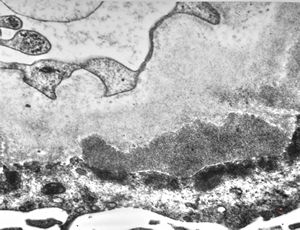

M,6y. | Alport syndrome- digital photo from the screen